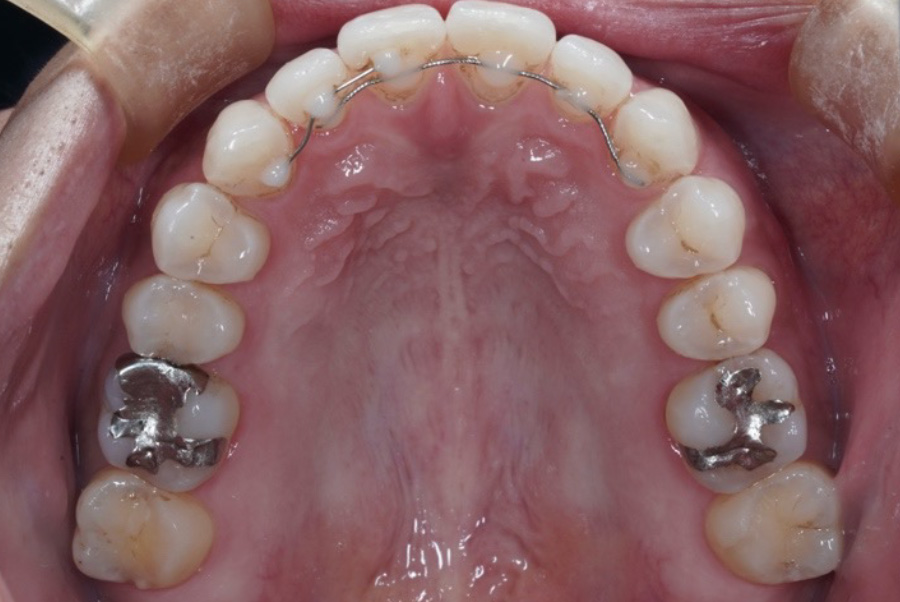

矯正治療終了時

現在6年経過リテーナーの役割とは?

②固定式リテーナー

(フィックスリテーナー)

前歯の裏側に細いワイヤーを接着して固定するタイプ。外からは見えません。